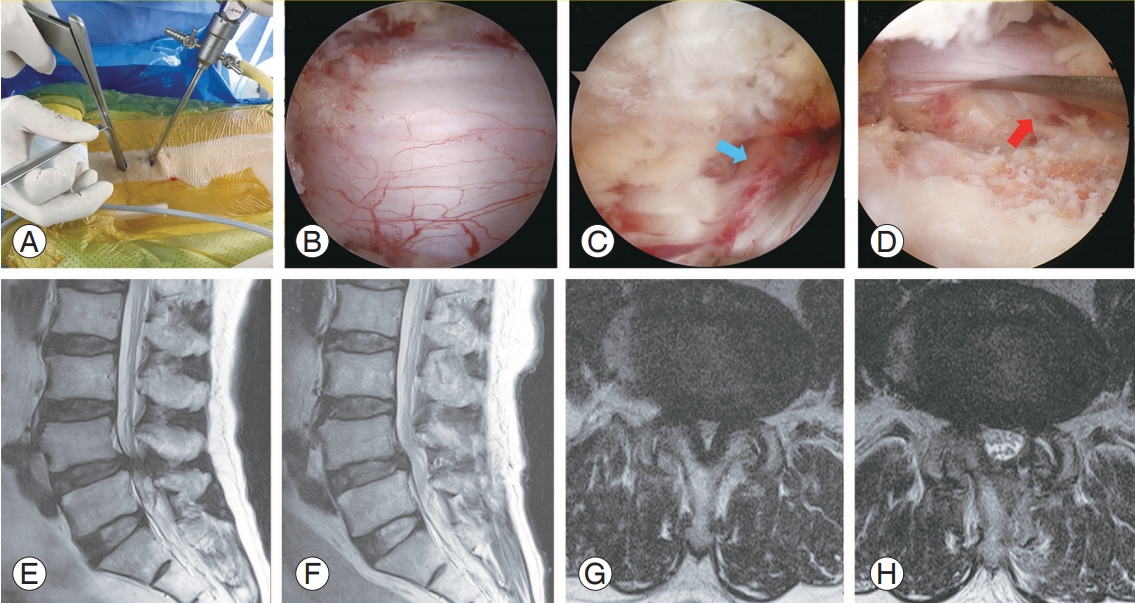

이 처럼 수요가 많지 않다 수요가 폭발한 것 처럼, 척추수술도 생각보다 수술이 간편하고 회복이 빨라지면서 관절경 수술수가 늘어나고 있습니다. 척추도 병변이 미세하게 작은 부분이라면 작은 절개창으로 그 부분만 수술 하므로써 증상 호전이 쉽게 가능하게 된다는 개념입니다.

개방창이 작아 미용적으로는 확실히 효과가 있으며, 시술 같은 수술이라고 생각하면 될 정도로 작은 흉터만 남게 됩니다. 하지만 수술자의 실력에 따라 오히려 내부의 근육의 파열이나 안의 조직, 인대들의 파괴가 될 수 있습니다. 오히려 개복술이 더 빠르고 예후가 좋을 수도 있습니다. 절개 후 근육을 적절하게 젖히고 접근시 직접적으로 척추 뼈를 보면서 수술하는 것이 신경을 건드리거나 실수할 확률이 더 적을 것이기 때문입니다. (물론 절개하는 과정에서 관절경에 비해 과도한 출혈이나 근육손상 등이 있을 수 있습니다. )

BESS 도 디스크를 목적으로 했던 Uniportal 에서 사용 범위가 확장되어 협착증에도 사용할 수 있는 Biportal 로 수술 가능하게 되었습니다.